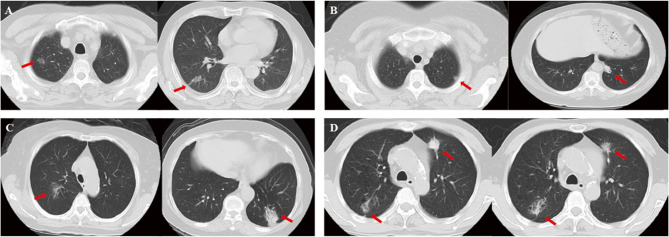

Purpose: Synchronous multiple primary lung cancer (SMPLC) is a special type. Currently, there are few reports on the clinical characteristics, genetic status, treatment strategies, and prognosis of SMPLC after radical surgery.

Methods: We retrospectively reviewed cases of SMPLC patients from January 2018 to October 2023. All patients underwent radical surgery and had genetic results using Next-generation sequencing (NGS) or Amplification refractory mutation system polymerase chain reaction (ARMS-PCR) for at least one lesion. Analysis was conducted on the clinical information, pathological types, genetic status, treatment strategies, and prognoses.

Results: We analyzed 72 patients with SMPLC in stage I-IIIA, and 64 of them were in stage IA. Epidermal growth factor receptor (EGFR) mutation was the most common gene, followed by Tumor protein 53(TP53) and Kirsten Rat sarcoma viral oncogene homolog (KRAS). Among the population with EGFR mutations, EGFR L858R, EGFR 19DEL, and EGFR G719X are common, accounting for 47.6%, 33.3%, and 7.2%, respectively. Among the 72 patients, 66 were lung cancer-free with a median follow-up time of 32 months and six patients experienced disease recurrence with a median Disease-free survival (DFS) of 24 months. For stage IA patients, DFS was correlated with the presence of pathological high-risk factors (combined small cell lung cancer, solid/micropapillae subtype) (P<0.001) and PD-L1 expression (P = 0.008), but was not correlated with the number of primary lesions, pathological stage (IA1, IA2, IA3), TP53/KRAS mutation, or status of EGFR sensitive mutation.

Conclusion: EGFR is a high-frequency mutation in early stage SMPLC. Radical surgery is a suitable treatment strategy for stage IA SMPLC patients, including those with EGFR sensitive mutations. Pathological high-risk factors and PDL-1 positive expression correlate with poorer prognoses in stage IA patients.